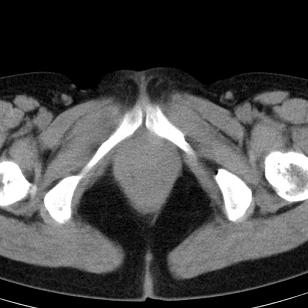

标题: CT19559:子宫及附件正常吗?

女,35岁,反复下腹部隐痛数月。

感觉上,子宫好象大了点

如果未孕,子宫体稍大,宫腔增宽,附件区未见异常密度影,还是建议结合b超检查为好,ct平扫对妇科没有优势。

子宫弥漫性等密度肿大,宫腔内缘见结节影突入腔内,子宫内膜异位可能